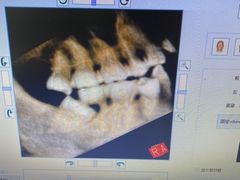

• 泰康拜博口腔(凯迪大厦店)

• -泰康拜博口腔(凯迪大厦店)

艾薇rain22 | 21-06-03